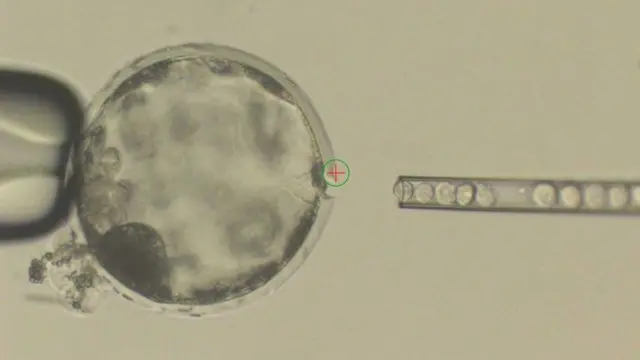

Para crearlos los científicos inyectaron en un embrión de cerdo células madre humanas, el tipo de células que pueden convertirse en cualquier tejido.

El embrión, que entonces pasa a ser una "interespecie" de humano y cerdo, es implantado en el útero de una cerda durante un máximo de cuatro semanas, un límite que obedece a motivos éticos.